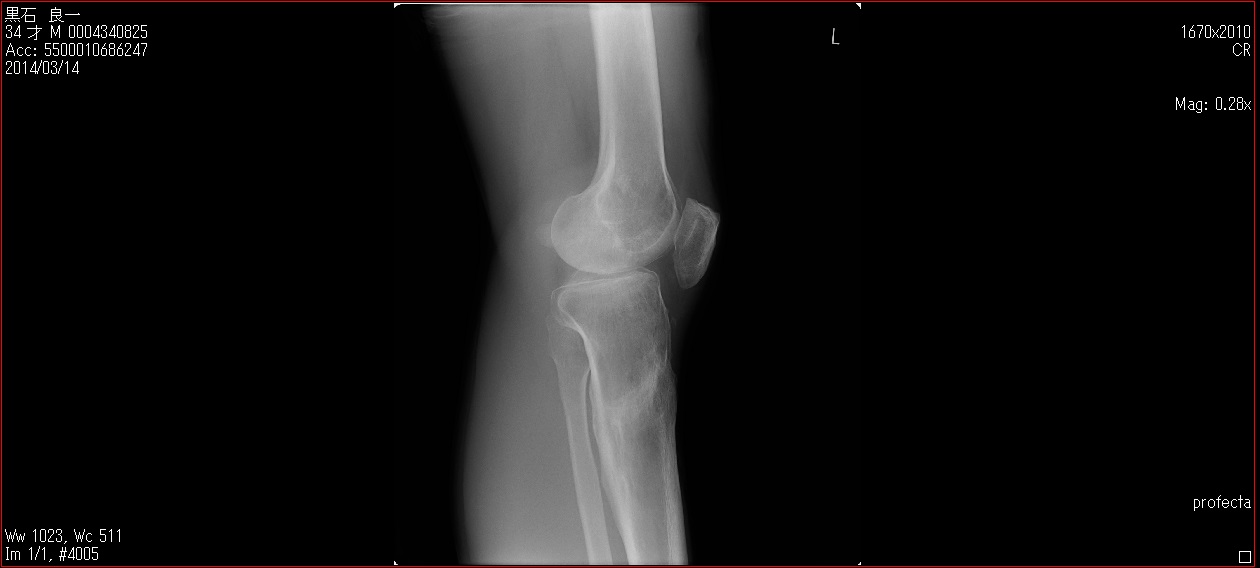

[Ortho] patella baja

Пациент 27 лет приехал для удлинения роста по эстетическим показаниям. Метод: крослатеральное двухэтапное удлинение голеней 4см и бедер 3 см.  Между этапами удлинения уезжал к себе домой в Японию на реабилитацию. Между этапами удлинения движения в коленных суставах разгибание полное сгибание 90-85. После выписки (февраль 2012) даны соответствующие указание постепенно возрастающей нагрузки и ЛФК коленных суставов.

В настоящий момент жалобы на ограничение сгибания в коленных суставах. Снимки прилагаются.

Вопрос: почему возникло такое осложнение? Поверьте приходилось удлинять намного больше, а тут всего на 3-4 см и такое осложнение на обеих конечностях у одного пациента?

Что можно сделать? У кого есть опыт лечения patella baja?